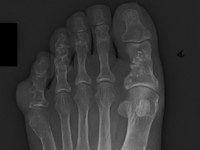

![Mafucci syndroom (click on photo to enlarge) [source: Miki Tanioka - www.intechopen.com - Creative Commons License 3.0] Mafucci syndroom](../../../images/mafucci-syndroom-1z.jpg) |

| Maffucci

syndroom |

Maffucci

Foto's: Miki Tanioka - Mafucci syndrome -

www.intechopen.com (Creative Commons License

3.0).